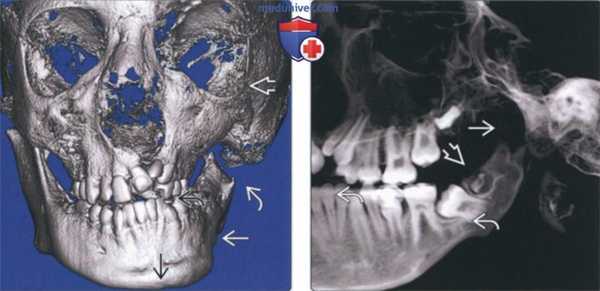

(Слева) На трехмерной реконструкции (КЛКТ, вид спереди) у мальчика 12 лет с гемифациальной микросомией III типа определяется врожденное отсутствие мыщелка и передней части ветви. Наблюдается задержка формирования левой половины нижней челюсти, левая глазница увеличена в размерах. Костная срединная линия нижней челюсти смещена влево, окклюзионная плоскость приподнята.

(Справа) На панорамной реформатированной КЛКТ определяется отсутствие мыщелка, уменьшение высоты тела нижней челюсти. В ветви видны формирующиеся зубы.

(Слева) На трехмерной реконструкции (КЛКТ, вид спереди) у пятилетней девочки с гемифациальной микросомией III типа определяется задержка формирования левой половины нижней челюсти. Угол нижней челюсти слева приподнят по сравнению с противоположной стороной. Сосцевидный отросток низко расположен.

(Справа) На панорамной реформатированной КЛКТ у этой же пациентки отсутствуют мыщелок и верхняя половина ветви слева. Суставная ямка и суставное возвышение не сформированы. Обратите внимание на скученность зубов.

(Слева) На панорамной реформатированной КЛКТ визуализируется расщепленный мыщелок справа. Визуализируется углубление в на верхней поверхности мыщелка, в остальном выглядящего нормальным. Обратите внимание на расширение верхнего суставного пространства. Контакт зубов сохранен.

(Справа) На панорамной реформатированной КЛКТ у этого же пациента визуализируется явно не измененный левый мыщелок. Обратите внимание на нормальные размеры верхнею суставного пространства по сравнению с противоположной стороной. (Слева) На сагиттальной КЛКГ у этого же пациента визуализируется углубление в центре правого мыщелка. Определяется уплощение суставного возвышения в результате ремоделирования и приспособления к измененной форме мыщелка.

(Справа) На сагиттальной КЛКТ у этого же пациента визуализируется левый мыщелок неправильной формы. На панорамном реформатированном изображении нарушение формы мыщелка достоверно не обнаруживалось. Определяется углубление в центре мыщелка и явное удлинение переднею края. (Слева) На корональной КЛКТ у этого же пациента определяется неглубокое углубление в центре правого мыщелка, разделяющее головку на внутреннюю и наружную части, и придающее ей характерную форму сердца. Кортикальная пластинка мыщелка непрерывна.

(Справа) На корональной КЛКТ у этого же пациента определяется V-образное углубление с наружной стороны мыщелка, разделяющего головку на внутреннюю (большую) и наружную (меньшую) части. Это нетипичный случай двухстороннего расщепления мыщелка.